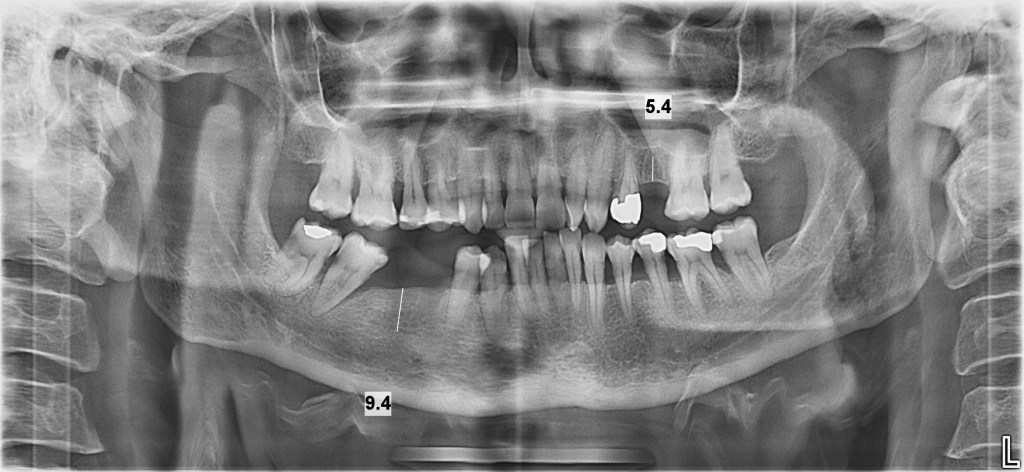

La primera visita a nuestra clínica dental es crucial para establecer una base sólida para tu salud bucal. Durante esta visita inicial, realizaremos una evaluación completa que incluye una ortopantomografía para obtener una visión completa de tu estructura dental, así como la exploración intra y extraoral para detectar cualquier problema existente o potencial. Además, utilizamos tecnología avanzada, como las aletas de mordida, para evaluar las caries entre dientes y el estado de restauraciones anteriores, entre otros aspectos. Esta evaluación exhaustiva nos permite diseñar un plan de tratamiento personalizado que se adapte a tus necesidades específicas y te brinde la mejor atención posible.